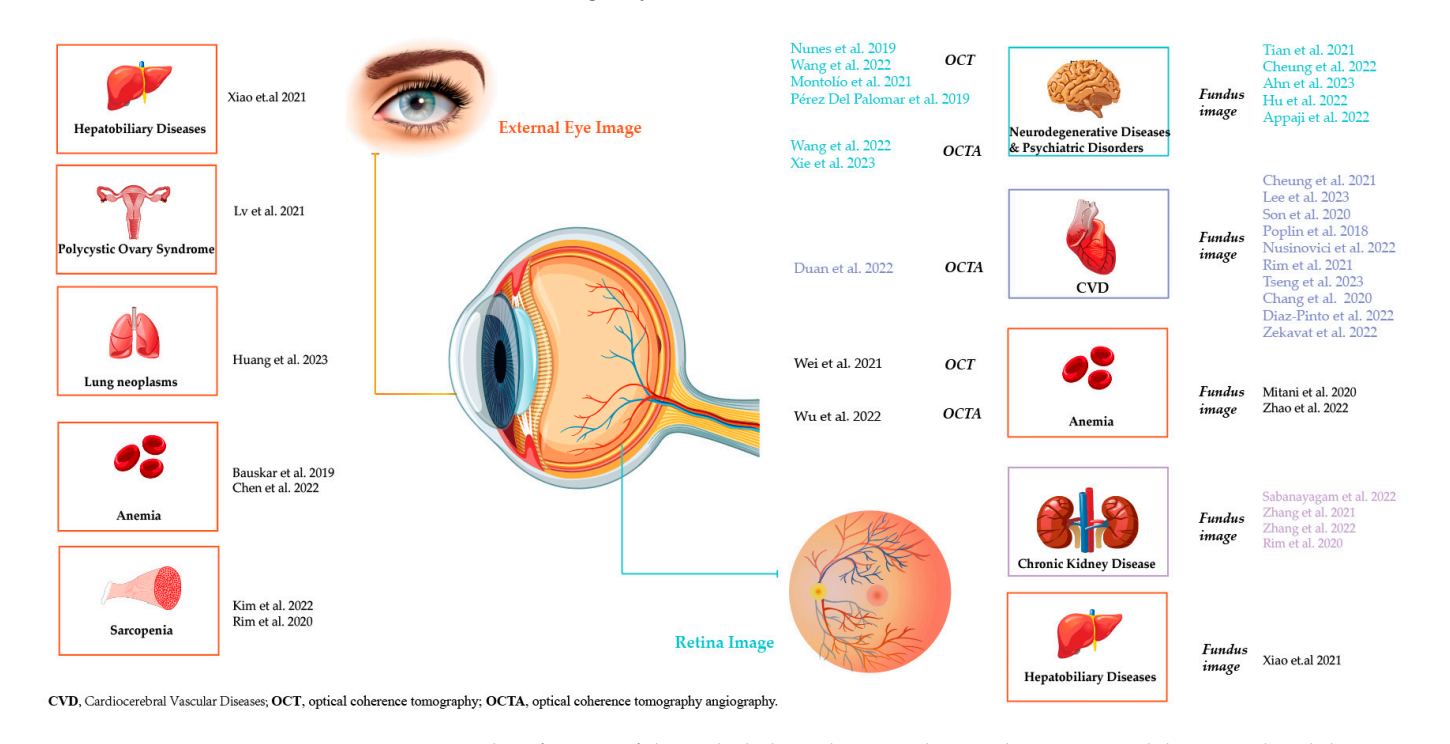

眼底看全身论文

论文:https://www.mdpi.com/2227-9032/11/12/1739

- 神经退行性疾病和精神障碍:使用OCT和眼底图像进行研究

- 心血管疾病(CVD):主要通过OCTA和眼底图像来研究

- 贫血:通过OCT、OCTA和眼底图像来研究

- 慢性肾脏疾病:通过眼底图像来研究

- 肝胆疾病:通过眼底图像来研究

- 多囊卵巢综合征:未指明使用的成像技术

- 肺部肿瘤:未指明使用的成像技术

- 贫血:通过OCTA来研究

- 肌少症:未指明使用的成像技术